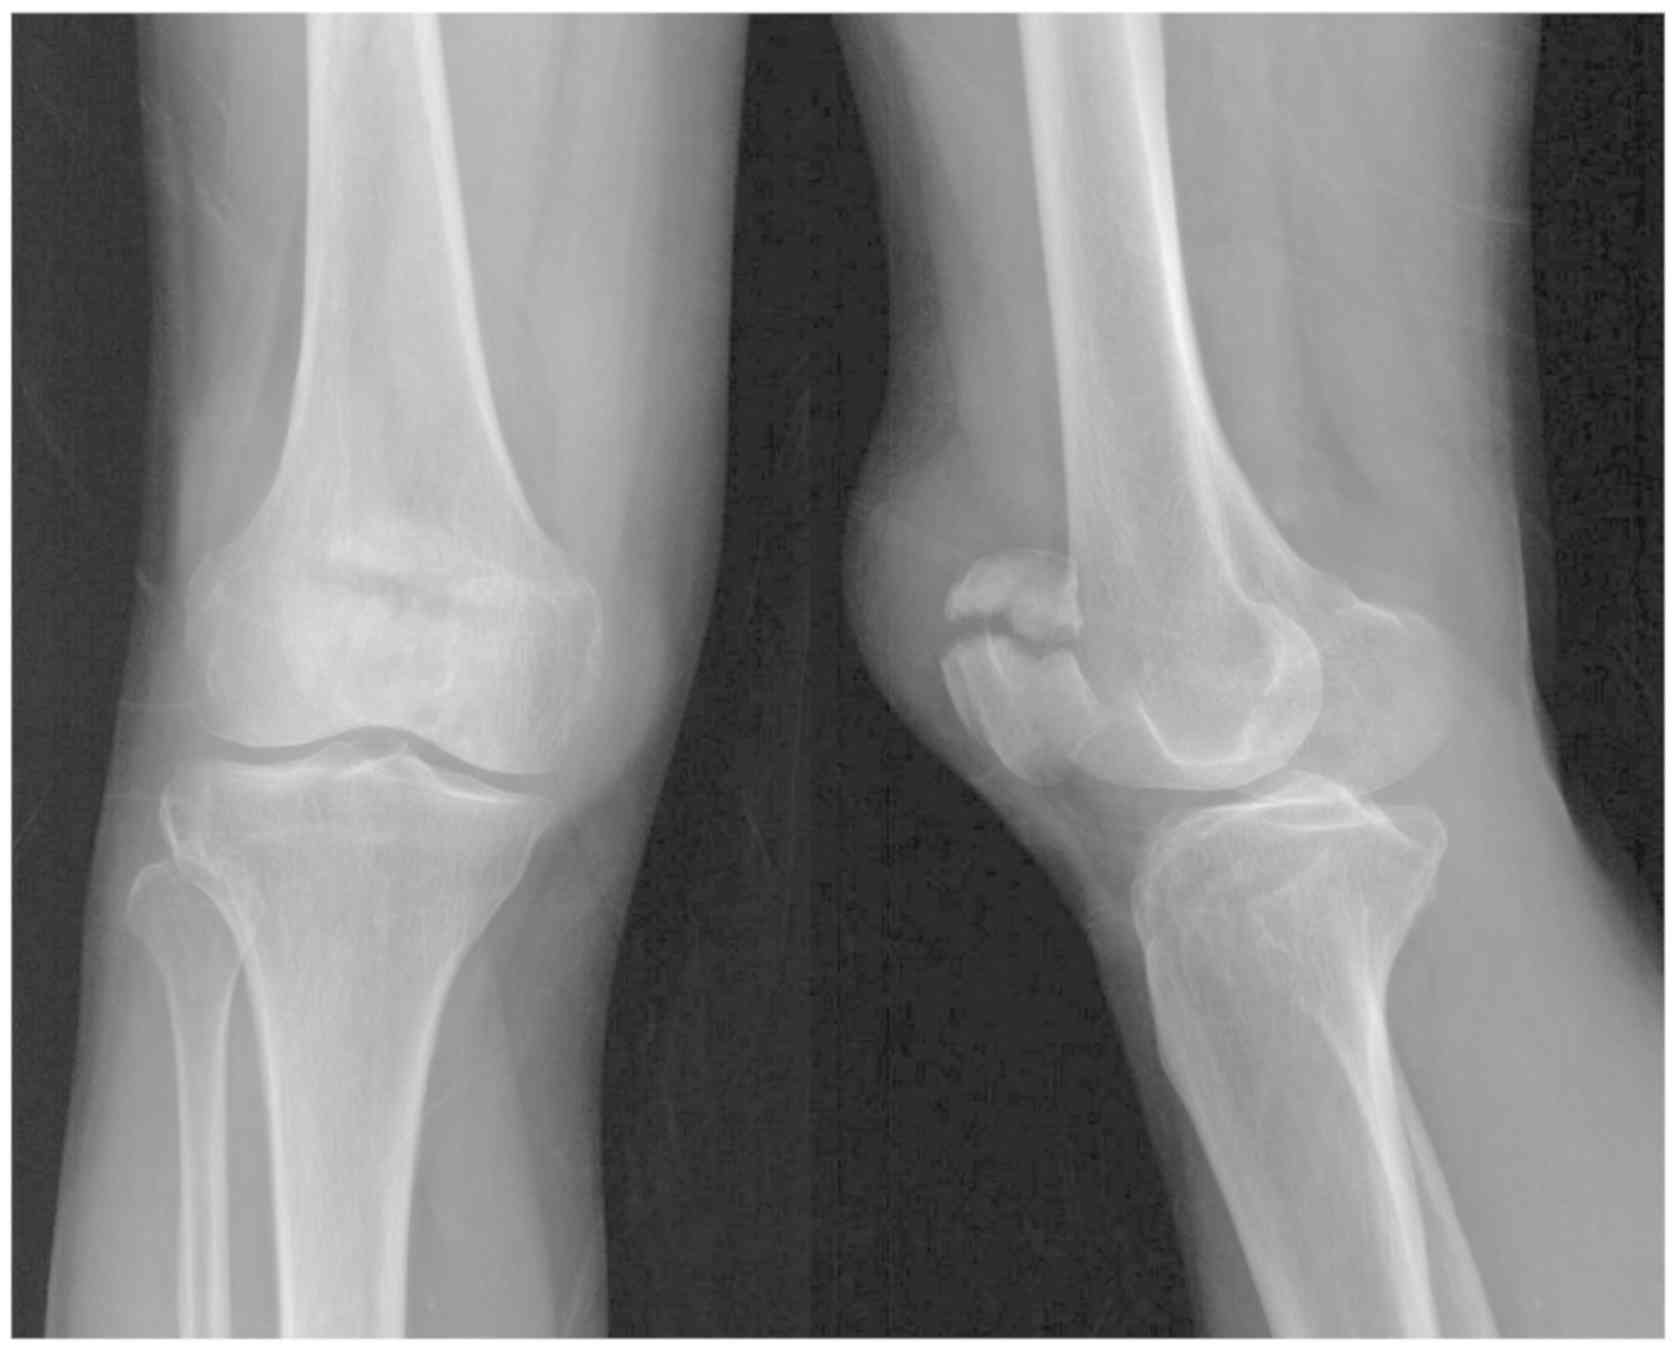

Figure 2.

Preoperative radiographs. The radiographsdemonstrated the displaced transverse fracture of the patella. The fracture line was near the proximal one-third of the patella.

If the minor transverse fracture fragment was at the proximal end and the major fragment was at the distal end of the patella (Fig. 2), the site of the proximal fragment would be confirmed and a ~3 cm longitudinal midline incision would be made from the proximal end of the patella down to the lower side of the proximal fragment (Fig. 3). The incision was from the skin to the prepatellar fascia. The soft tissues were pulled downwardto expose the fracture line. Any hematomas and traumatic bone debris were removed, and the articular cavity was washed with normal saline solution. Manipulative reduction was made with the assistance of two towel clamps applied percutaneously. During the reduction procedure, the knee joint was flexed and extended several times, and the fragments were squeezed and pressed against to the femoral condyle to facilitate the reduction of the articular surface. A K-wire was then drilled superiorly and percutaneously into the patella from the lower side of the apex for temporary fixation following the reduction (Fig. 4A). A C-arm fluoroscopy was used to confirm the anatomical reduction of the articular surface (Fig. 4B), and then the prepatellar fascia was sutured.